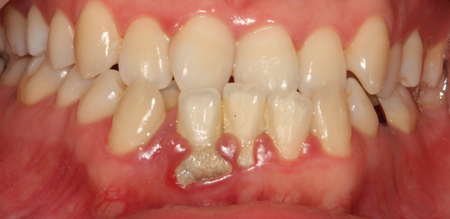

치주치료

청담네오플란트는 치주치료를 통하여 치아를 살릴 수 있는 기회를 놓치지 않습니다.

치주염(잇몸병)은 치아에 붙어있는 치석 및 세균 등에 의한 염증반응으로 잇몸뼈가 상실되는 질환을 말합니다.

초기에는 잇몸이 붓거나 잇몸에서 피가 나는 증상이 나타나며 계속 방치하면 치아를 발치해야 할 수도 있습니다.

치주치료는 이러한 치석 및 세균 등을 제거하여 잇몸뼈를 안정된 상태로 유지하는 시술을 말하며, 청담네오플란트에서는 치의학박사 / 전문의가 직접 시술하고 있습니다.

치주치료 전후사진

B

A